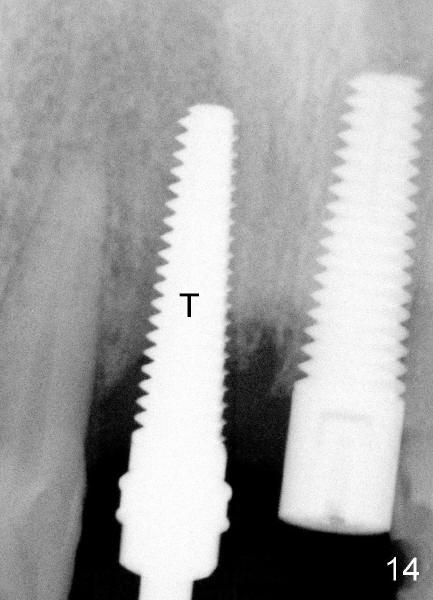

X-ray in Fig.13 is taken two months after implant removal and immediately before 2nd implant placement.  Round tapered osteotomes (2 and 3 mm) are inserted into the socket.  Then a 4.5x20 mm tapered tap (Fig.14: T) is driven into the socket first by a slow handpiece and second by drill/tap extender (without wrench).  Finally a 5x20 tapered implant is torqued into the recipient socket with some degree of resistance (Fig.15: I).